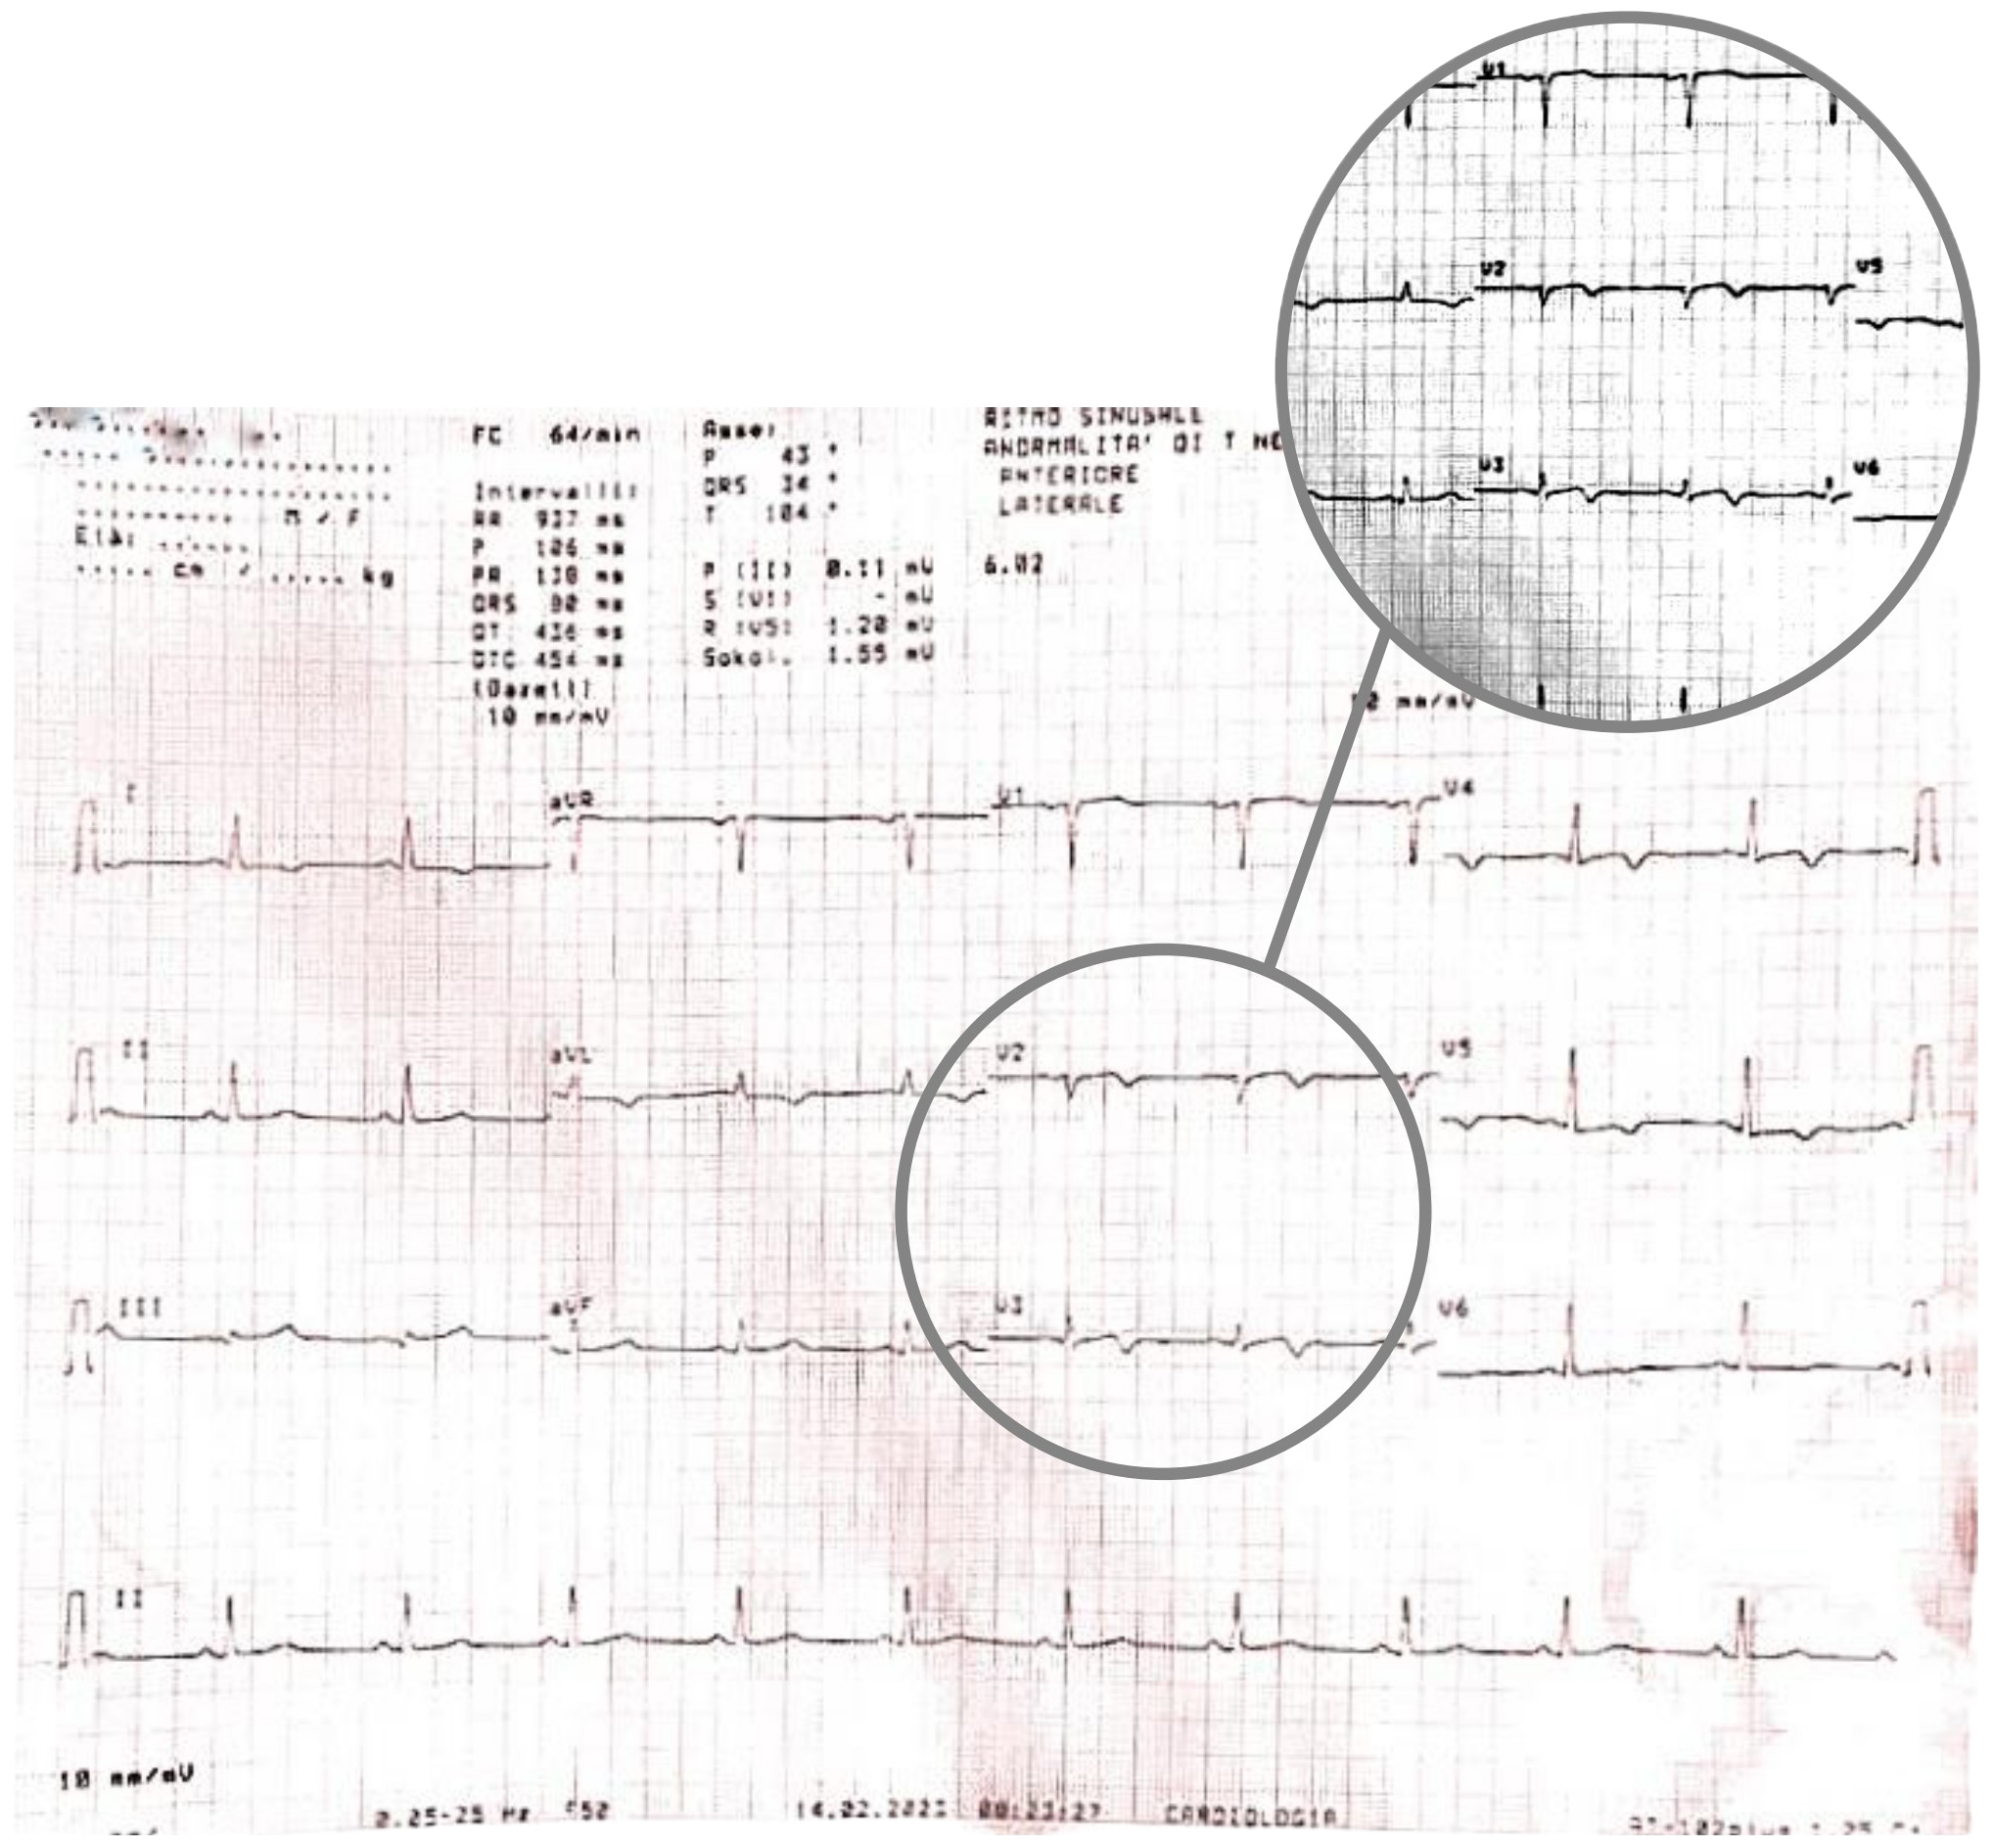

A few minutes later, the patient experienced a further episode of chest pain, which occurred at rest, but was of greater intensity and duration, and had no clear triggering factors, another 12-lead ECG was performed and showed some differences compared to previous recordings: symmetrically inverted T waves were evident in leads V2 and V3, this time resembling a type B Wellens pattern (Fig. 5 — ECG). As discussed above, these ECG patterns, in a patient admitted for chest pain with slightly elevated serum cardiac markers and negative 3-hour hs-troponin T delta, should raise suspicion of Wellens Syndrome, which is highly specific for critical stenosis of the LAD.

Fig. 5.

Fig. 5.ECG showing symmetrically inverted T waves in leads V2 and V3, resembling a type B Wellens pattern. ECG, electrocardiogram.